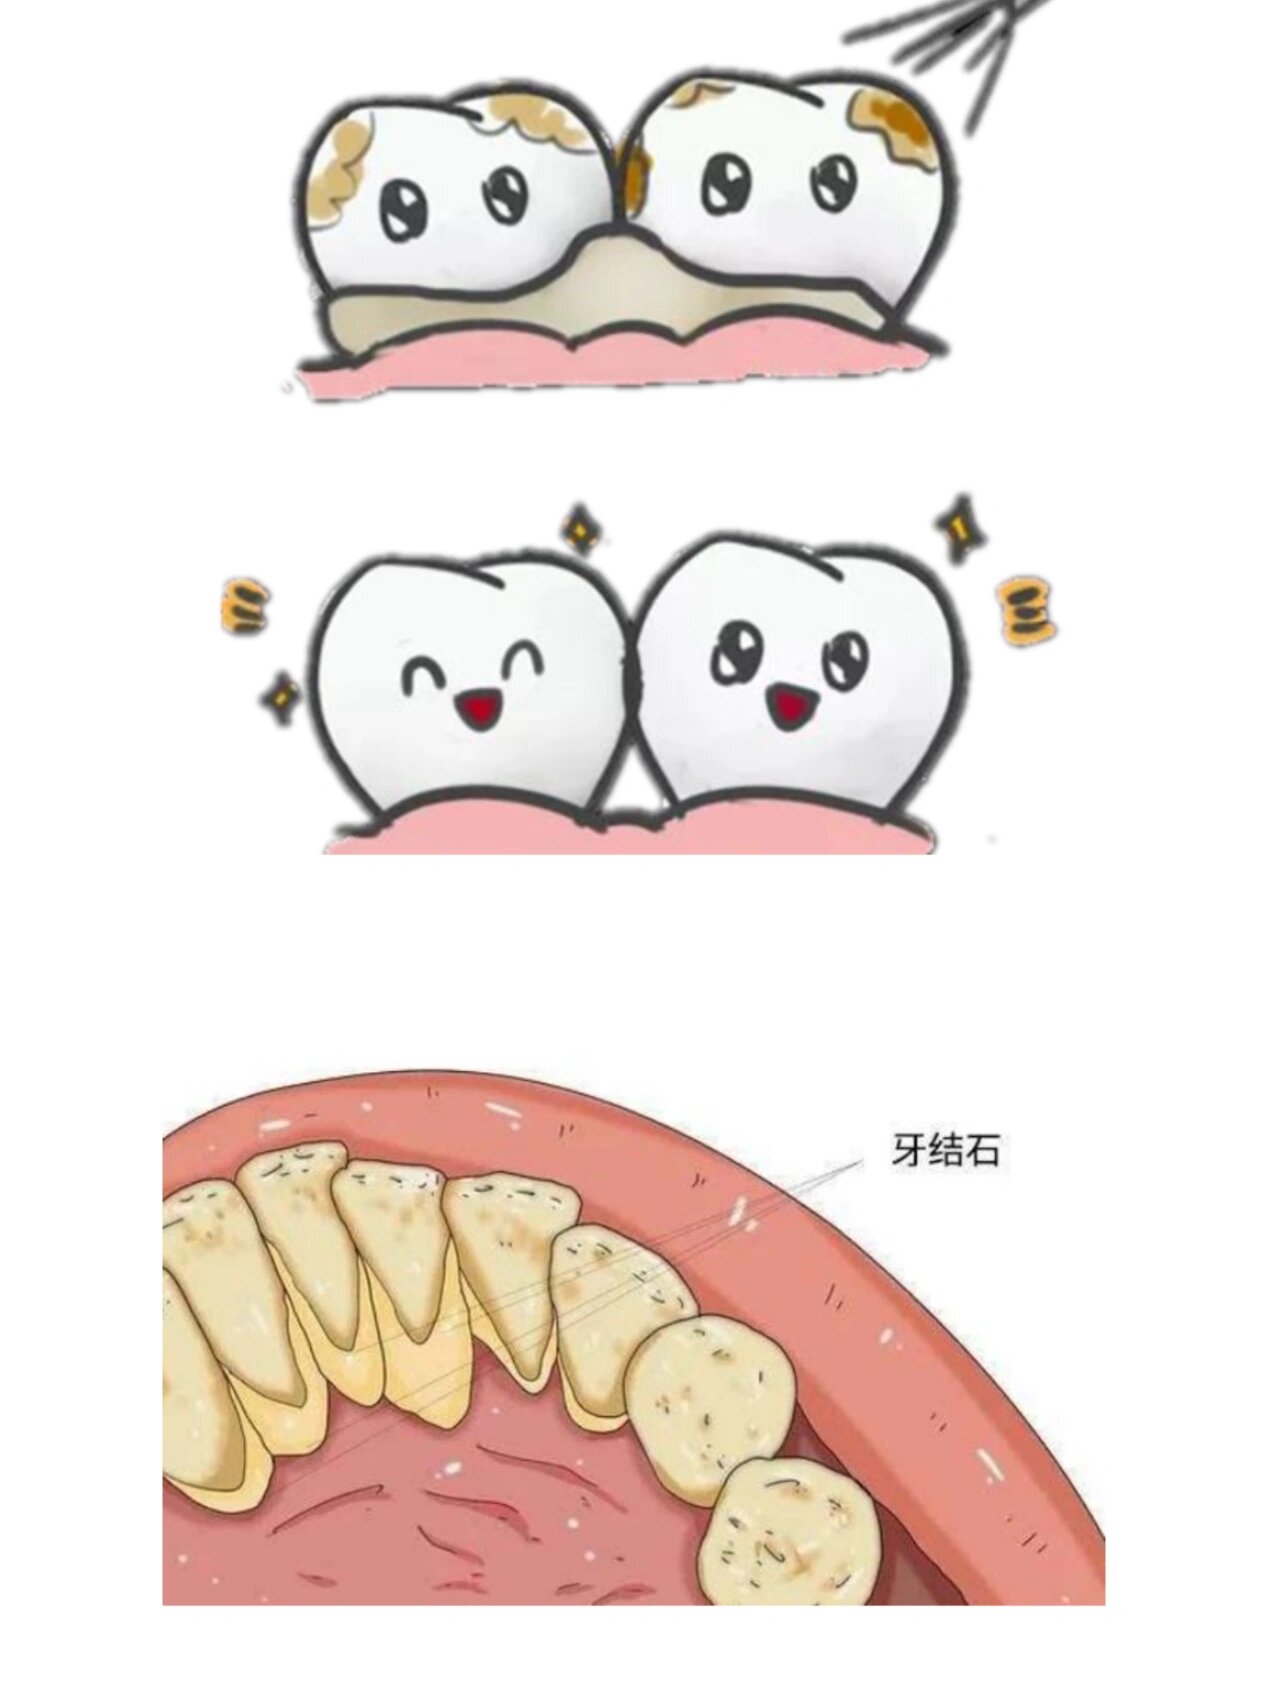

漫画牙结石

你知道牙结石是怎么生成的吗? 口腔内,可是存在着许多细菌呢!